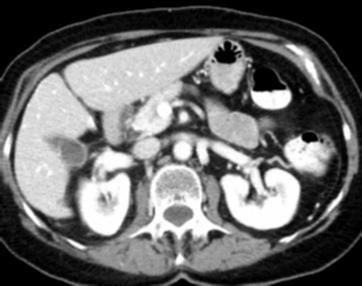

Due to the constraints of the imaging device and high cost in operation time, computer tomography (CT) scans are usually acquired with low intra-slice resolution. Improving the intra-slice resolution is beneficial to the disease diagnosis for both human experts and computer-aided systems. To this end, this paper builds a novel medical slice synthesis to increase the between-slice resolution. Considering that the ground-truth intermediate medical slices are always absent in clinical practice, we introduce the incremental cross-view mutual distillation strategy to accomplish this task in the self-supervised learning manner. Specifically, we model this problem from three different views: slice-wise interpolation from axial view and pixel-wise interpolation from coronal and sagittal views. Under this circumstance, the models learned from different views can distill valuable knowledge to guide the learning processes of each other. We can repeat this process to make the models synthesize intermediate slice data with increasing inter-slice resolution. To demonstrate the effectiveness of the proposed approach, we conduct comprehensive experiments on a large-scale CT dataset. Quantitative and qualitative comparison results show that our method outperforms state-of-the-art algorithms by clear margins.